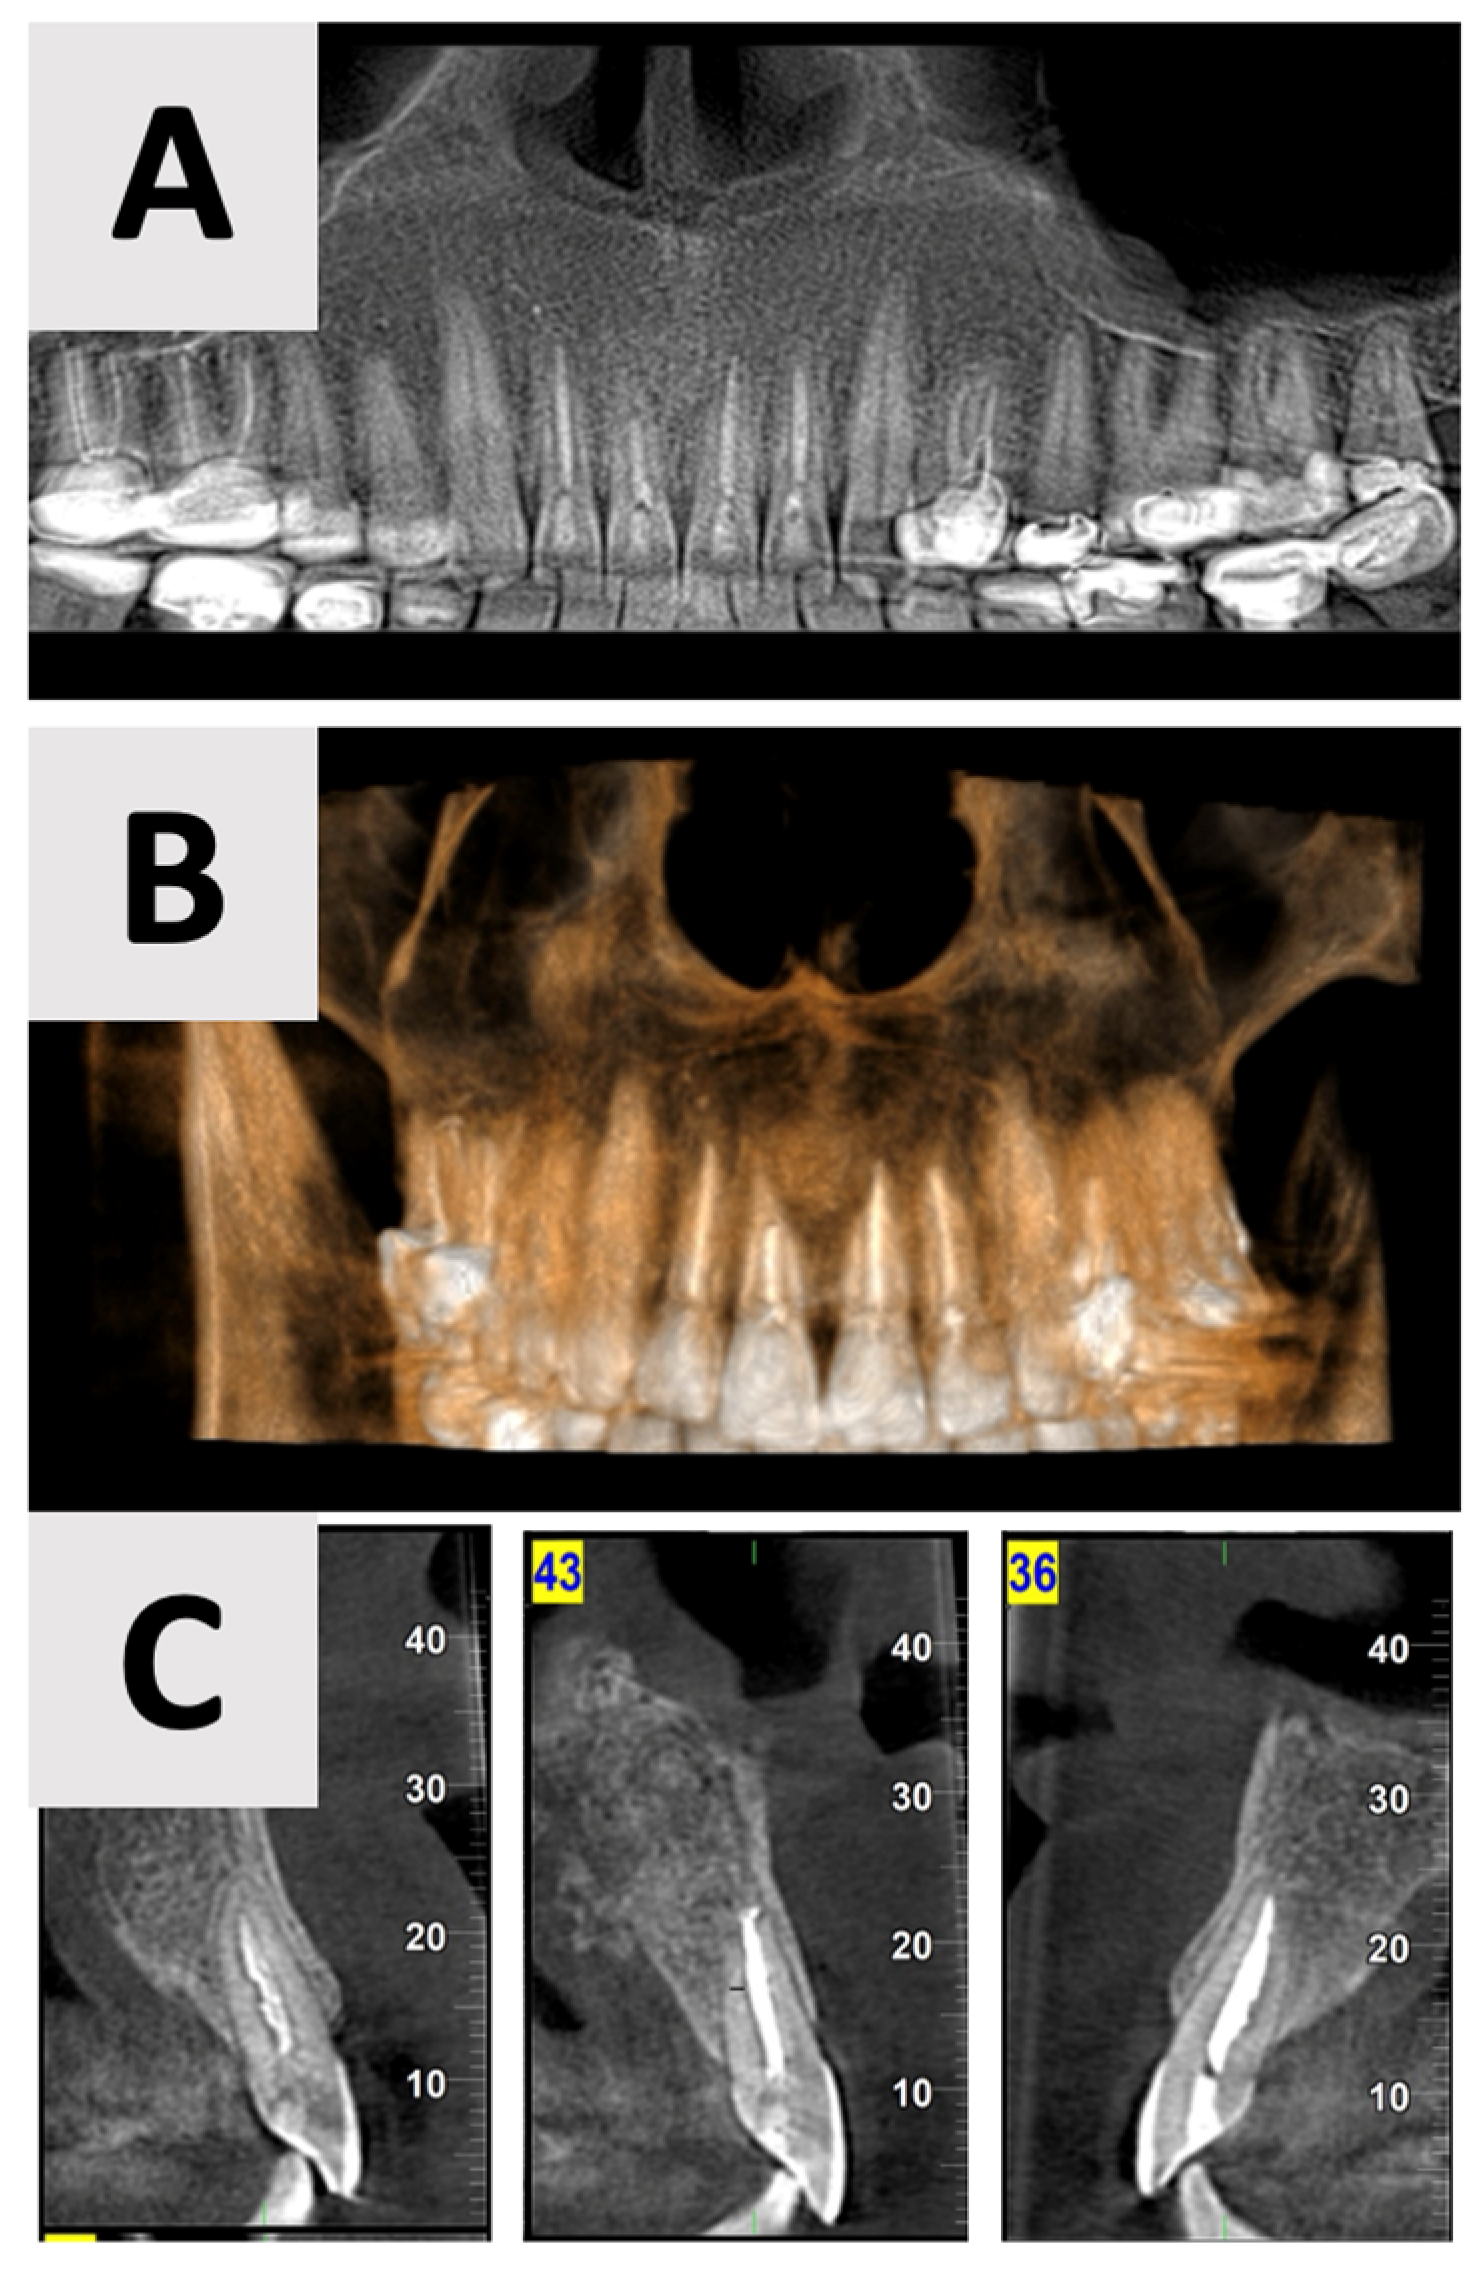

Figure 2.

Radiographic evaluation of cyst six months following marsupialization. (A) Panoramic reconstruction illustrating the initial defect site prior to enucleation. (B) Cyst regression and improved bone density in the affected area. (C) Paraxial view.

The findings indicated favorable cyst regression and improved bone density in the affected area. Based on these results, it was determined that the marsupialization had created optimal conditions for the next phase of treatment. Consequently, the decision was made to proceed with cyst enucleation, marking the transition to the definitive surgical management of the lesion.